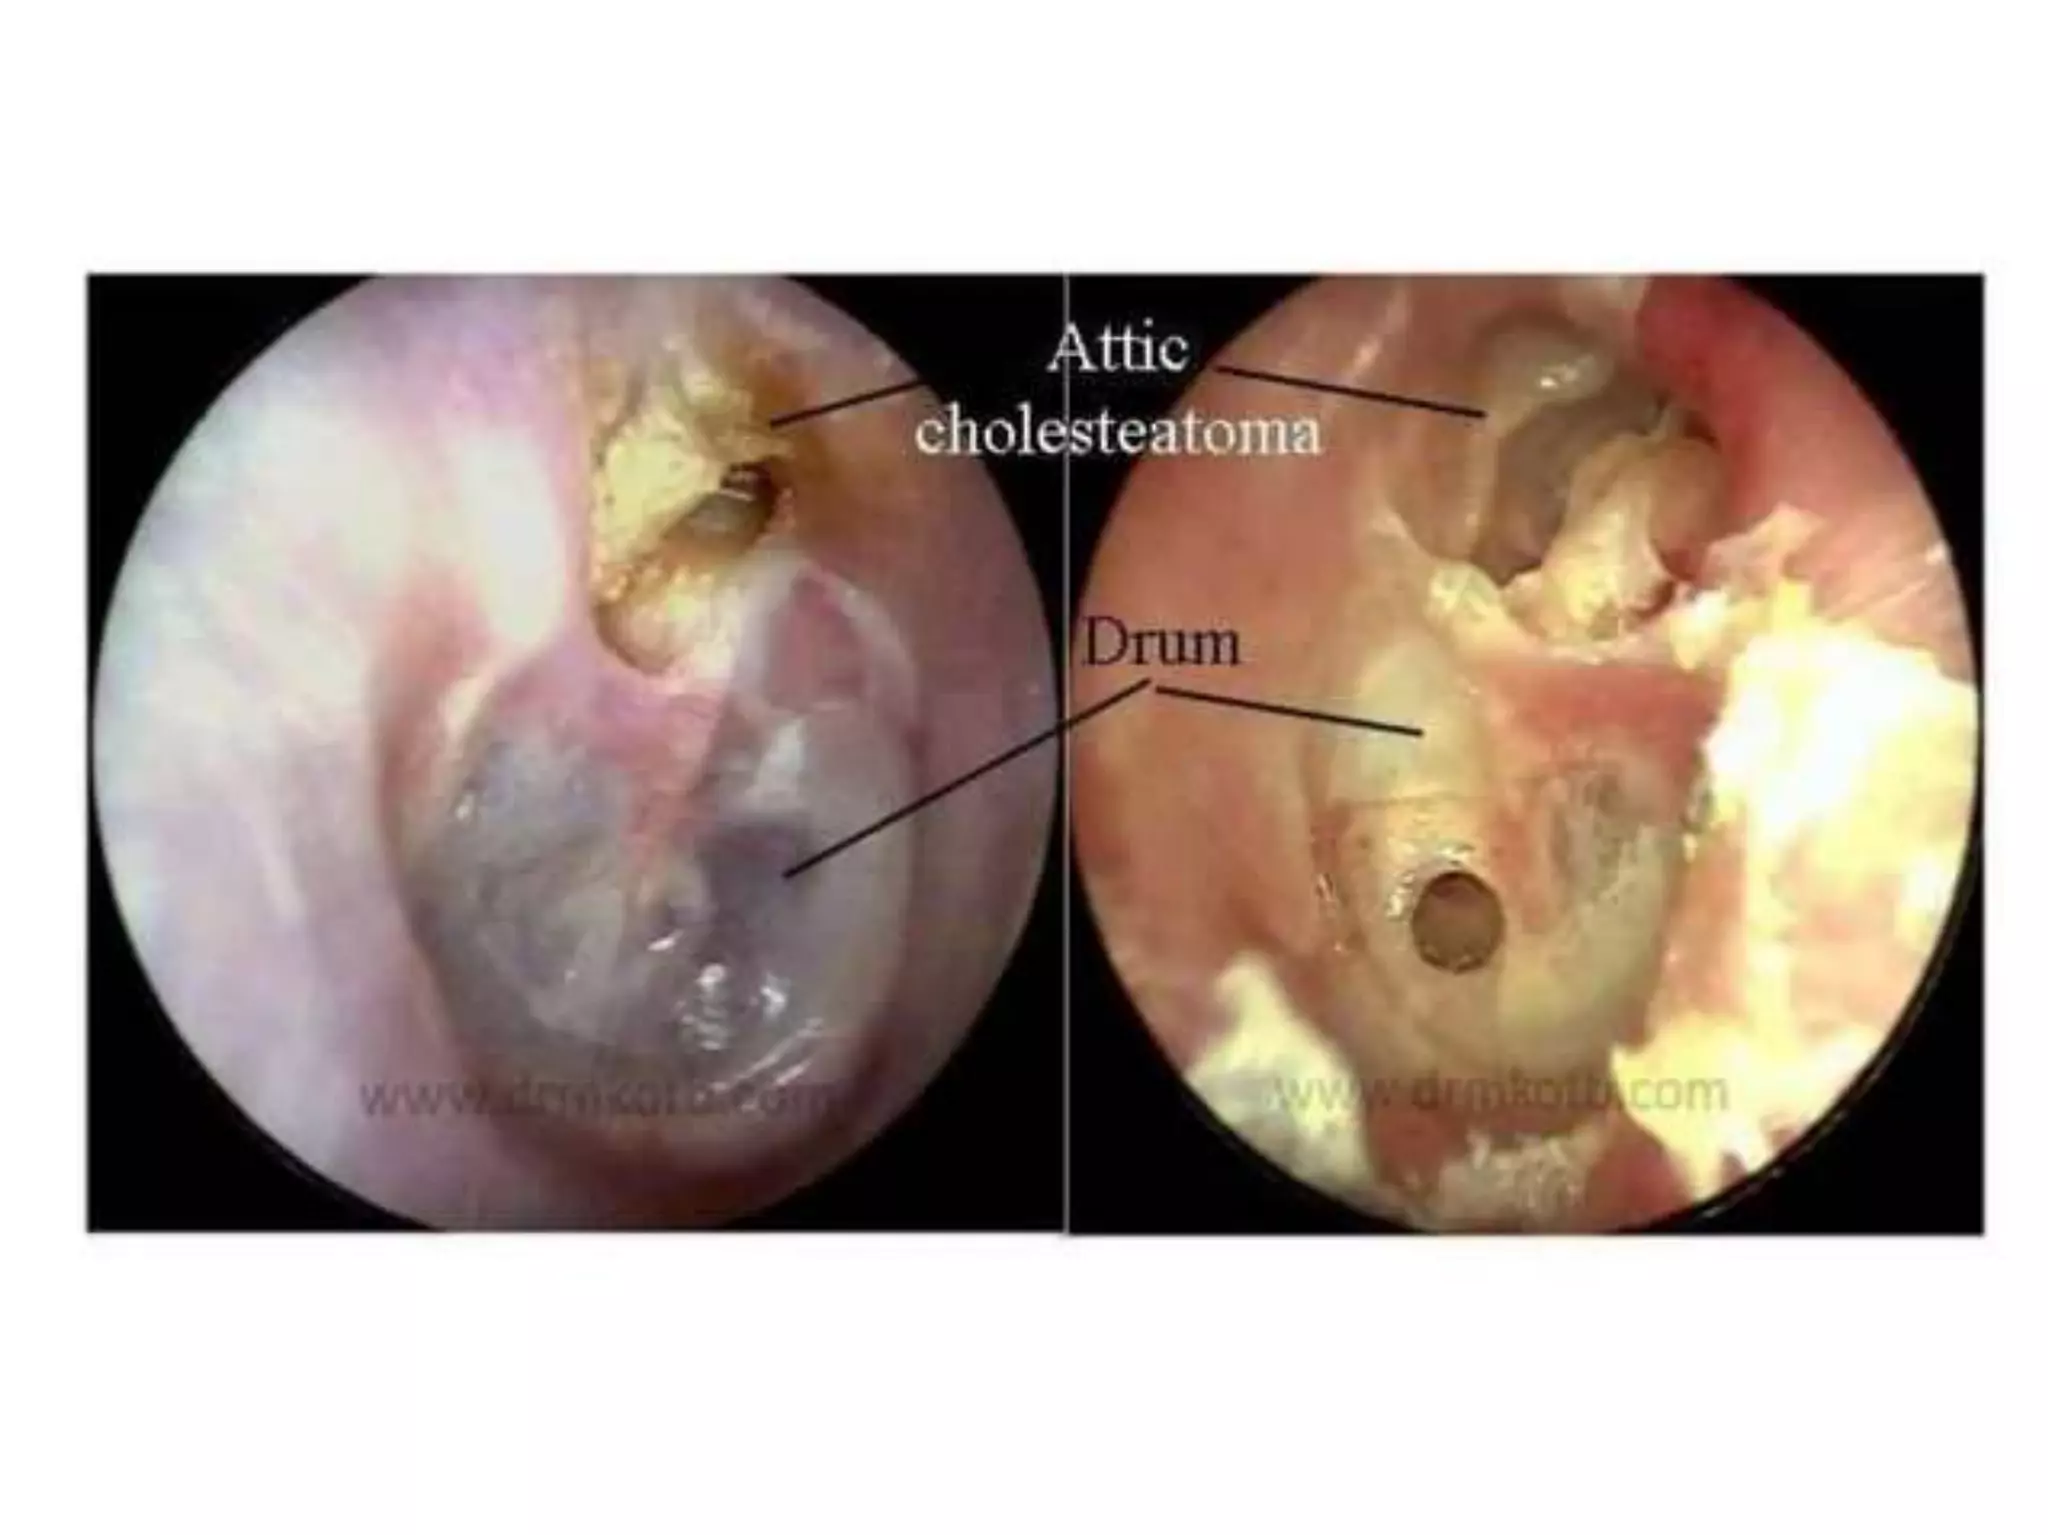

Chronic otitis media is a chronic inflammation of the middle ear and mastoid cavity that presents with recurrent ear discharge through a perforated eardrum. It has several subtypes depending on the state of the eardrum perforation and epithelium. It can be caused by prior acute otitis media, genetics, environment, eustachian tube issues, gastroesophageal reflux disease, craniofacial abnormalities, or immune deficiency.